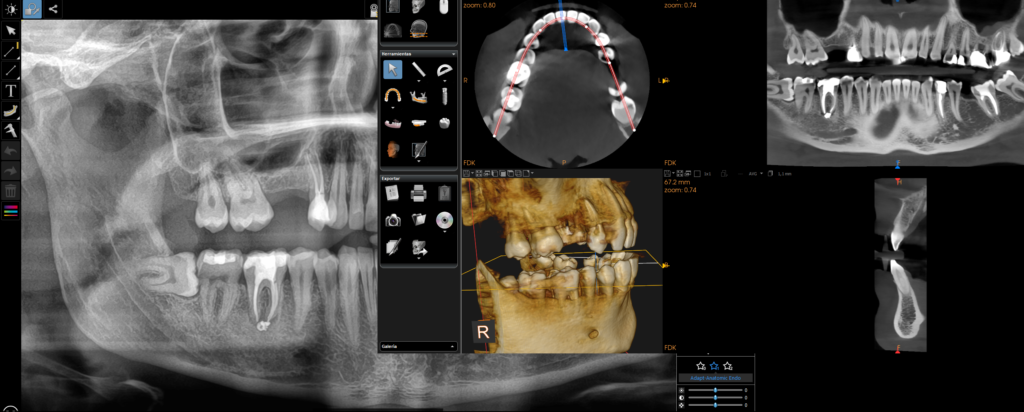

ÚLTIMA TECNOLOGÍA DENTAL

Contamos con la última tecnología y con técnicas avanzadas que permiten mejorar los resultados y haces que los tratamientos sean más cortos.

Contamos con la última tecnología y con técnicas avanzadas que permiten mejorar los resultados y hacer que los tratamientos sean más cortos.